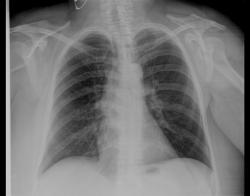

Коллеги, прошу высказать ваше мнение по-поводу отмеченой стрелкой тени. В анамнезе: злокачественная опухоли молочной железы и желудка, выполнена левосторонняя мастэктомия.

Это крупный очаг неоднородной плотности, это очень походит на периферический рак или на очаг Гона. И еще трахея смещена вправо.

похоже на обызвествление реберного хряща.

Посмотрите внимательно, коллеги, а где эта тень на прямой?

Справа от грудной клетки в мягких тканях.

Это не хрящ. Эти тень в проекции 10 сегмента, если смотреть на прямую.

Браво Flaqman! это обызвествленная фиброаденома правой молочной железы

Итак. Татьяна Валентиновна наглядно ответила, что "патологический процесс" в молочной железе может "найти своё отображение" на рентгенограмме органов грудной полости, произведенной в прямой стандартной проекции.

и в боковой тоже...